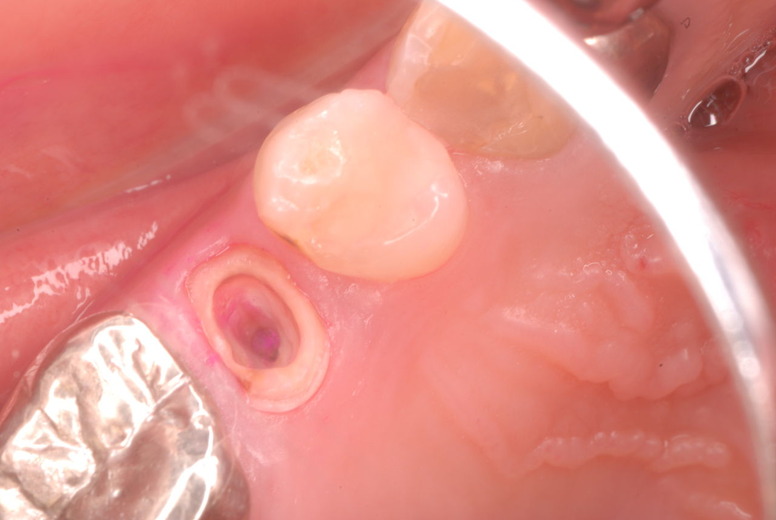

写真左下の親知らずが痛くなり抜歯しました。その後歯茎を除去して虫歯を露出させる処置を二回ほどしています。

レントゲンでは小さいですが、こう言う虫歯が一番怖いのです。